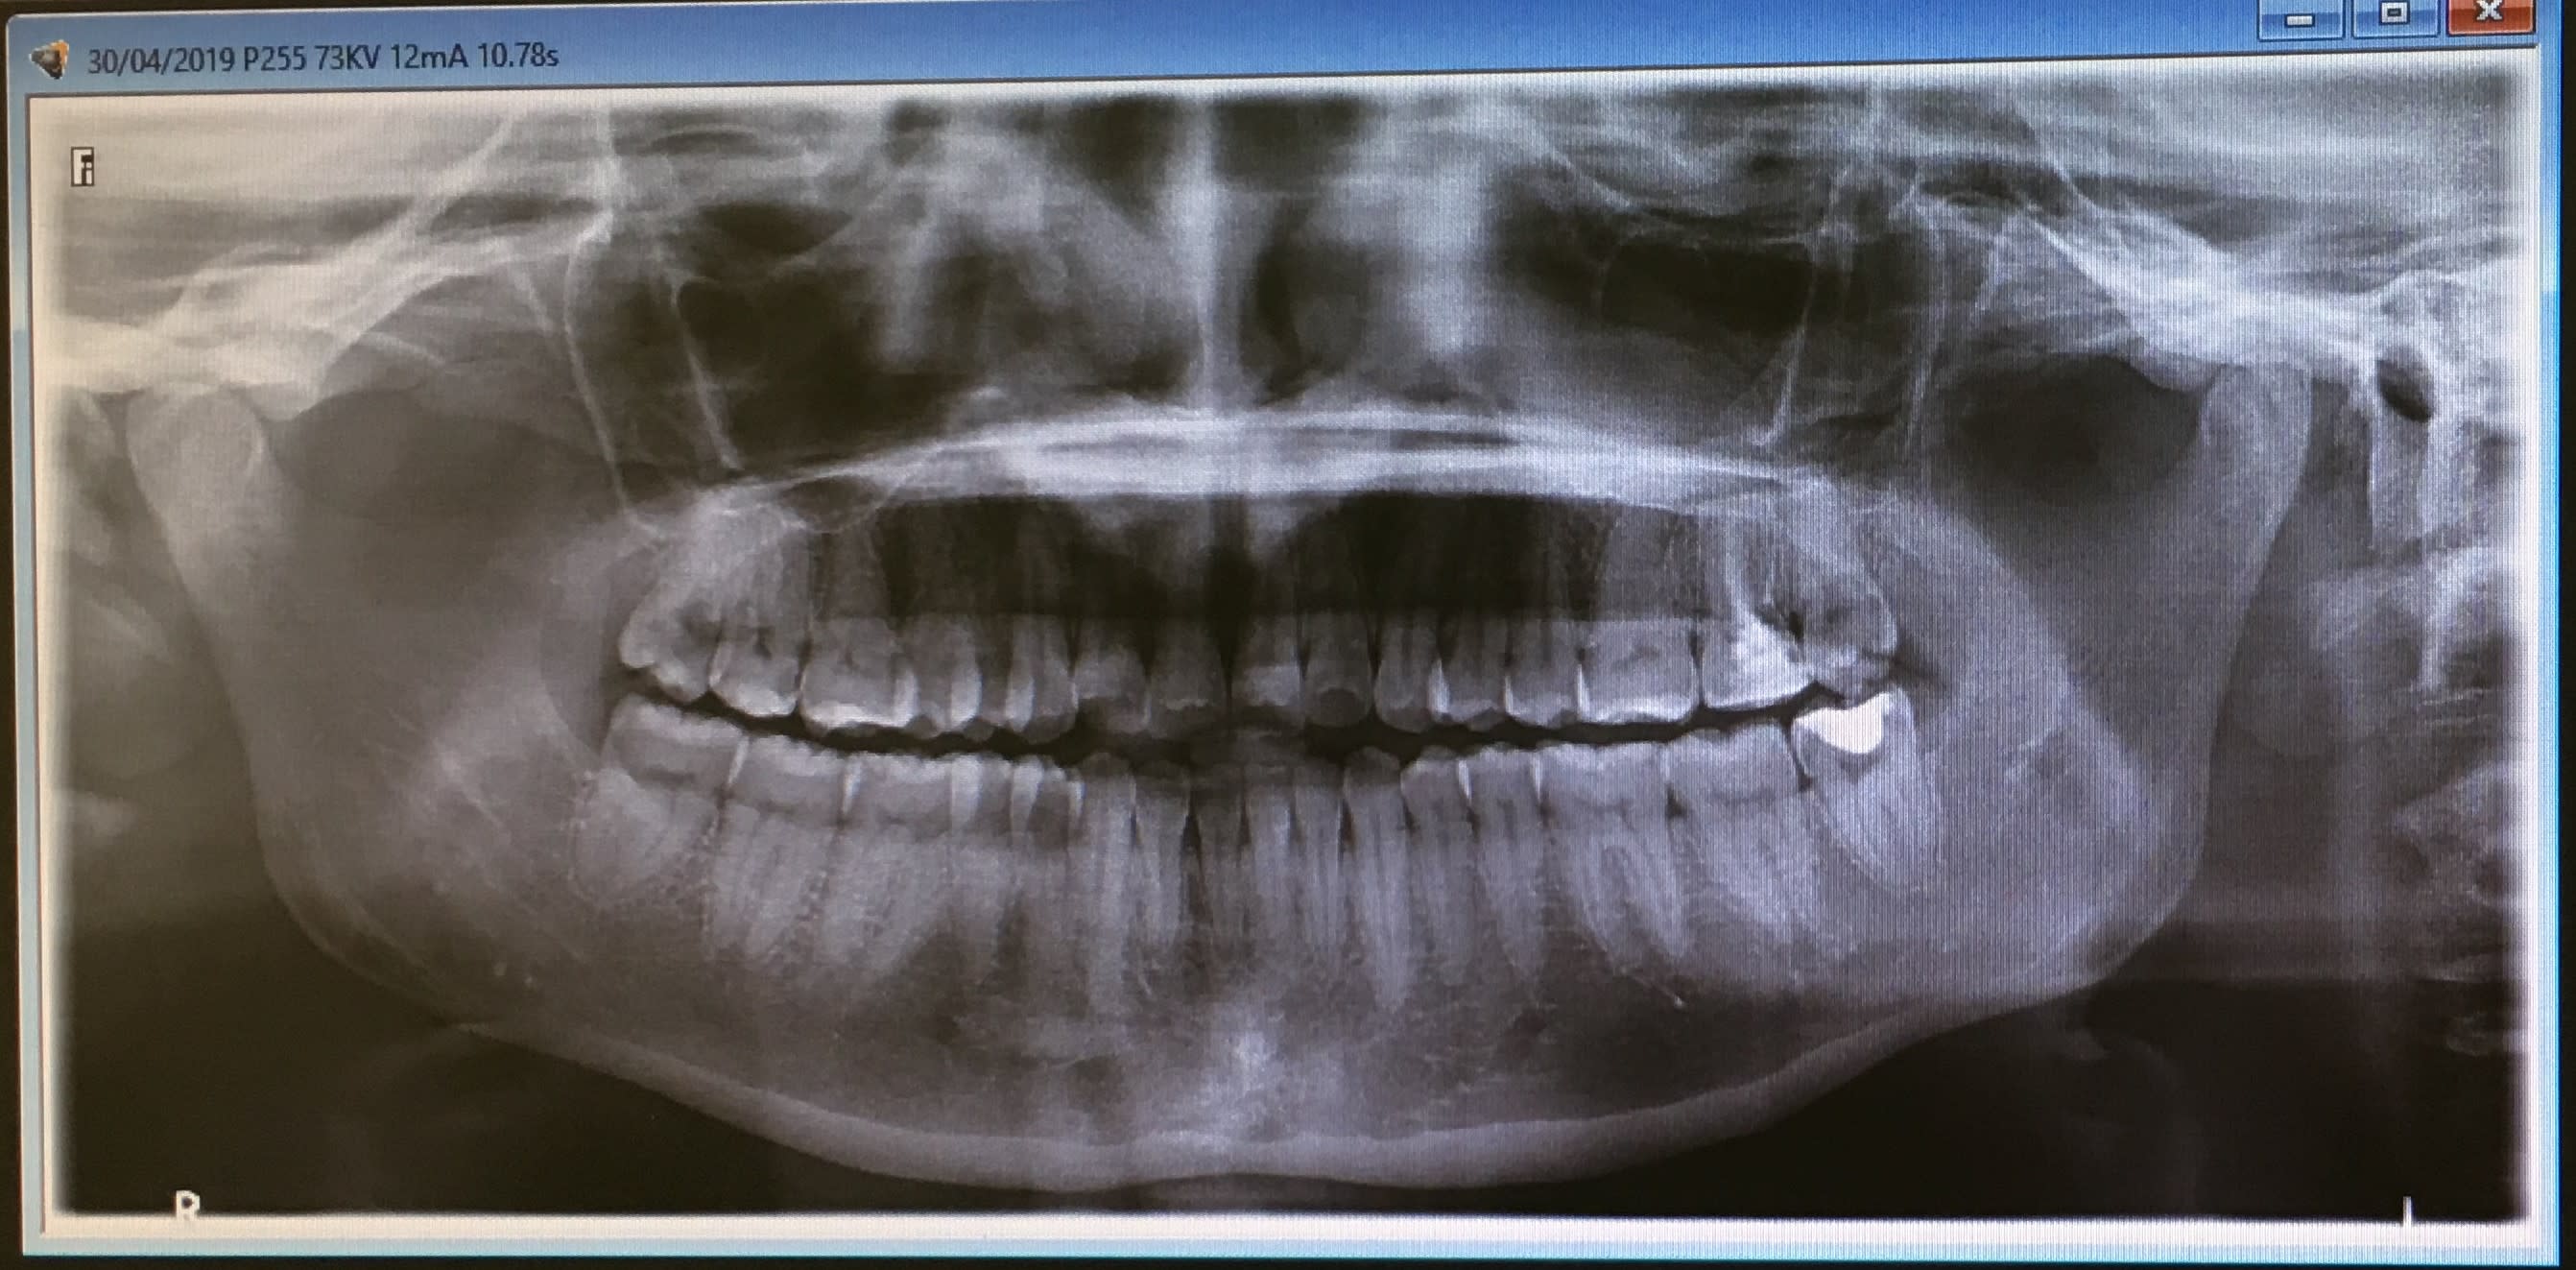

La patiente se représente le lendemain avec des d+ qui n'ont pas diminué, je décide alors d'extraire. Je réalise une pano.

>Q2: Ya t'il une façon de voir sur la premier pano que la dent n'allait pas sortir facilement. Sur la 2eme je vois que les racines sont pe joint.

- sur la pano la dent n'a pas l'air méchante mais elle est déjà bien amochée par la cavité donc cela peut vite se compliquer

Sur la pano cela semble une dent plutôt facile. Un coup d’élévateur en distal jusqu'à ce que tu dilates l'os, puis davier si nécessaire. Difficile de faire une séparation de racine vu qu'elles sont fusionnées apicalement..

nan mais sérieusement elle était pas difficile cette 8 !

Intervention mal préparée .

C’est vrai qu’elle n’avait pas l’air bien méchante a la radio mais voila l’exemple d’une dent bien pourrie qui fait galerer ... plus ça va moins je fais les dds du bas,ce qui est bien dommage parce qu’honnetement j’aime la chirurgie,j’ai envi d’apprendre mais pour 40 e enclavée,80 grand prince quand elle est incluse .... ça me désespère. Limite ça me plairait d’etre Avec un stom une demi journée par semaine en milieu hospitalier pour ça.